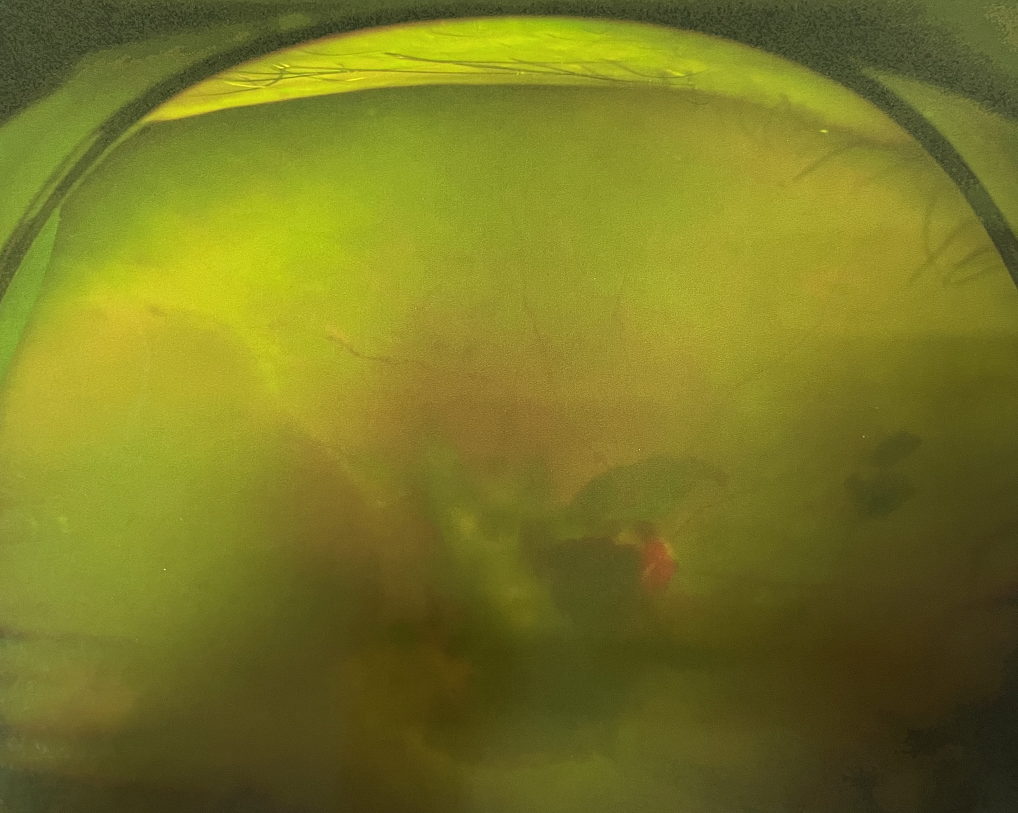

眼底出血不是獨(dú)立的眼病,而是由于眼球自己的病變和某些全身疾病的并發(fā)癥導(dǎo)致眼底的視網(wǎng)膜或脈絡(luò)膜出血,如果出血量大就會(huì)進(jìn)入到眼球的玻璃體內(nèi),從而影響視力,如果沒有得到恰當(dāng)?shù)闹委熆蓭砀鼑?yán)重的并發(fā)癥造成失明。

眼底出血的患者,如果出血量少,而且在視網(wǎng)膜周邊部可能沒有明顯癥狀,患者僅感到眼前有黑影浮動(dòng);如出血量多,將嚴(yán)重影響視力,甚至完全被黑影所遮擋僅剩光感;如出血位于視網(wǎng)膜的黃斑區(qū),患者視野中心區(qū)被暗影遮擋,周邊尚有部分視力。

先是散瞳檢查眼底,可以明確眼底出血的性質(zhì),出血部位和出血量有多少。眼B超檢查,對(duì)于眼底出血量特別多,無法看清眼底的患者,就需要進(jìn)行眼部B超檢查,以了解出血量,出血部位、有無合并視網(wǎng)膜脫離;還可以明確是否患有視網(wǎng)膜或脈絡(luò)膜的腫瘤。